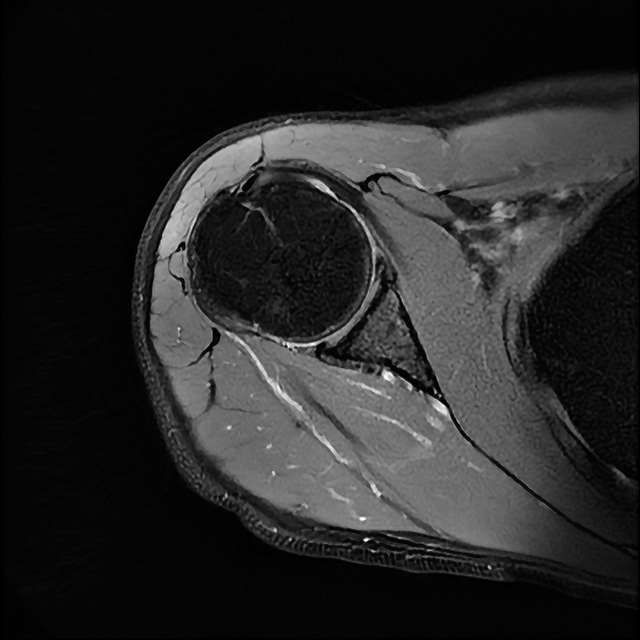

오른쪽 어깨 와순파열 및 점액낭염이 보인다고 하는데 상태를 알고 싶습니다

MRI 사진상 와순파열 점액낭염 등이 있다고 하는데..심한 상태인가요?

MRI상 와순파열, 회전근개 부분파열 등이 있으며 일부 염증소견이 있습니다.

주사, 약물, 물리치료 등에 통증이 호전을 보인다면 경과관찰을 해볼 수도 있겠지만 어깨관절의 불안정성 및 통증이 심하신 상태라면 관절경을 이용하여 수술적 치료를 받으시는 것을 추천드립니다.